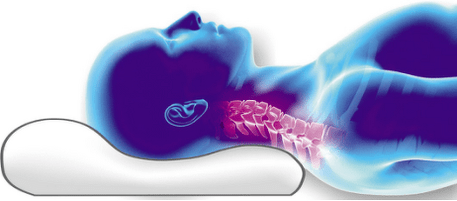

- Dùng sai gối khi ngủ.

Tại sao cần có gối chỉnh hình?

Một chiếc gối chỉnh hình cho bệnh thoái hóa đốt sống cổ là một thứ không thể thiếu, vì nó cho phép bạn đạt được sự thư giãn hoàn toàn của các sợi cơ và tránh chèn ép các mạch máu dẫn đến tuần hoàn kém. Gối chỉnh hình nên như thế nào? Đây là dấu hiệu của nó:

- Sự hiện diện của một hình dạng giải phẫu (con lăn hoặc con lăn, một chỗ lõm đặc biệt cho vai);

- Đệm cổ nâng đỡ đầu một cách cẩn thận và tạo ra sự hỗ trợ thích hợp cho đốt sống cổ. Gối chỉnh hình có 2 gối đỡ có độ cao khác nhau, dùng để

các tư thế cơ thể khác nhau, thích hợp để ngủ nằm ngửa và nằm nghiêng. Một nhóm chuyên gia đã phát triển một thiết kế gối có rãnh (một hoặc hai) dưới vai để hỗ trợ cổ và đầu đúng cách khi ngủ - đặc biệt là nằm nghiêng. Hình dáng có phần lõm cho vai giúp bạn tìm được tư thế thoải mái và giữ thẳng cột sống.

các tư thế cơ thể khác nhau, thích hợp để ngủ nằm ngửa và nằm nghiêng. Một nhóm chuyên gia đã phát triển một thiết kế gối có rãnh (một hoặc hai) dưới vai để hỗ trợ cổ và đầu đúng cách khi ngủ - đặc biệt là nằm nghiêng. Hình dáng có phần lõm cho vai giúp bạn tìm được tư thế thoải mái và giữ thẳng cột sống. - Độ đàn hồi của vật liệu là khả năng của vật liệu lấy lại hình dạng sau áp lực.

- Ngủ trên gối xốp chỉnh hình (lựa chọn gối là tùy từng cá nhân);